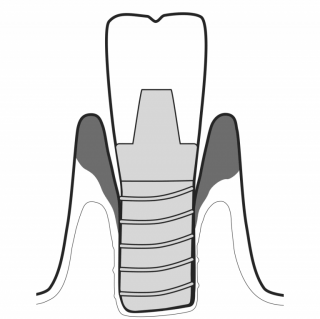

IMPLANTOLOGY

- GBT is the only predictable solution for implant maintenance.

- Treating mucositis with GBT can help prevent peri-implantitis.

- GBT is indispensable for pre-treatment, post-operative and life long maintenance of implants.

MAINTAIN IMPLANTS

GBT steps deliver a minimally invasive method to protect implant surfaces. 04 AIRFLOW® and 05 PERIOFLOW® with PLUS Powder are gentle on implant surfaces, while metal instruments may scratch.

TREAT MUCOSITIS

While gentle on peri-implant tissues, AIRFLOW® with PLUS Powder safely reaches and cleans any ruggedness on implant surfaces for optimum biofilm removal. GBT is the state-of-the-art approach to implant maintenance.

TREAT PERI-IMPLANTITIS

PERIOFLOW® with PLUS Powder removes subgingival biofilm with unequalled limitation of peri-implant bleeding.The PIEZON® PI Instrument removes the remaining abutment calculus thereby preserving the implant surface.